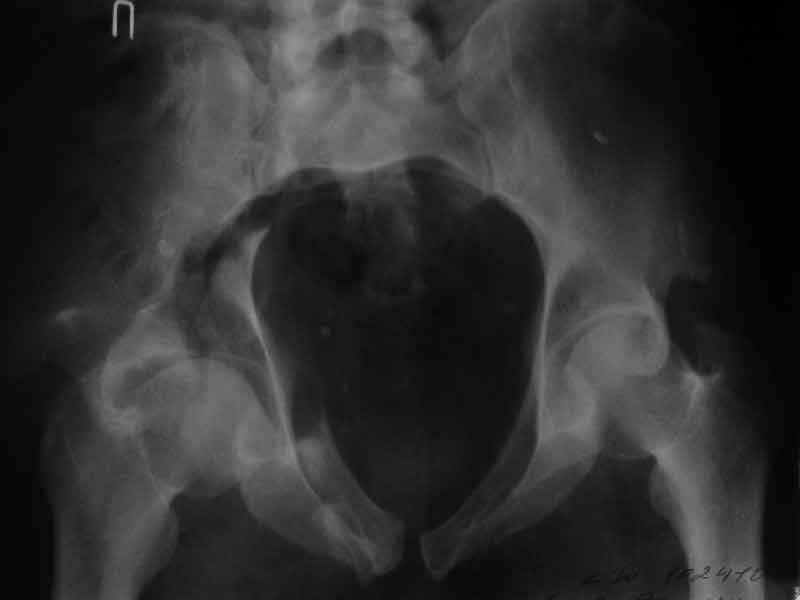

Уважаемые коллеги, нужна помощь, поступил больной с переломом лонной и седалищной кости слева, перелом вертлужной впадины слева, нестабильный вывих левой бедренной кости. Попытки вправить бедренную кость- безуспешны. На данный момент находится на скелетном вытяжении, посоветуйте какую тактику ведения данного больного выбрать оптимально.Спасибо.

Досылаю рентгенограмму

> Досылаю рентгенограмму

Бессмысленно заниматься лечением повреждений вертлужной впадины по такой рентгенограммам, попытайтесь вправить вывих и отправить в лечебное учреждение, где занимаются лечением подобных повреждений.

Поверьте, ни в коем разе не хочу Вас обидеть, но если нет возможности сделать качественные рентгенограммы в нескольких проекциях, то грамотное лечение таких повреждений практически невозможно.